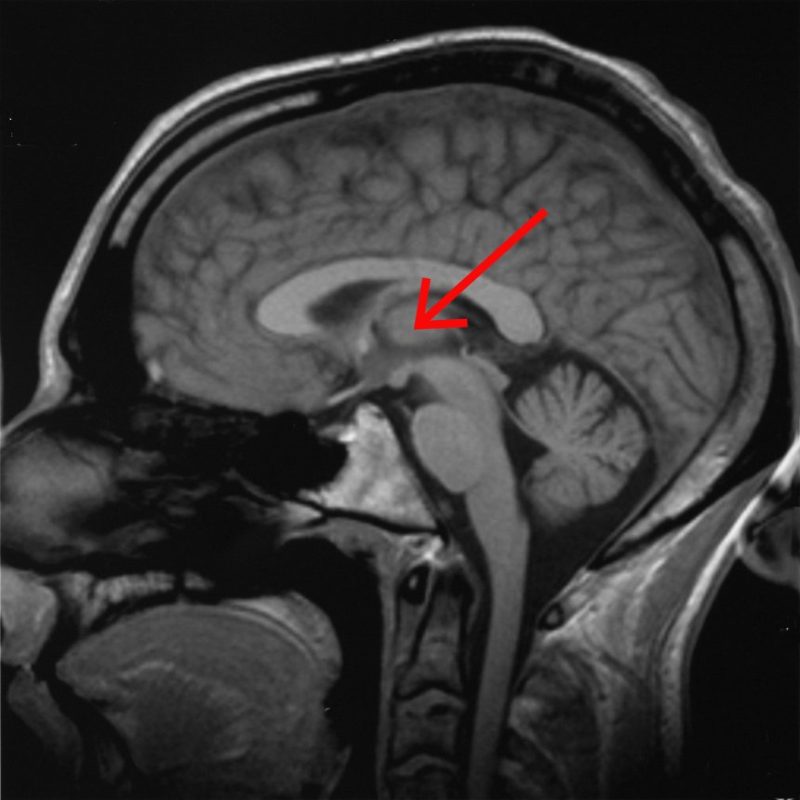

আমাদের জেগে থাকা, ঘুমিয়ে পড়া, ঘুমিয়ে স্বপ্ন দেখা, ঘুম থেকে জেগে ওঠা, বা ধ্যানমগ্ন হওয়া – মস্তিষ্কের এই বিভিন্ন অবস্থাগুলো এবং পঞ্চ ইন্দ্রিয়ের সাহায্যে সংগ্রহ করা বিভিন্ন তথ্য মস্তিষ্কের যে সকল অংশ দ্বারা নিয়ন্ত্রিত হয় তাদের মধ্যে প্রধান হলো – “সেরিব্রাল কর্টেক্স”, “মিডব্রেইন”, ও “থ্যালামাস” যারা একে অপরের সাথে বেশ কিছু নিউরাল লুপ-র মাধ্যমে যোগাযোগ স্থাপন করে।

সেরিব্রাল কর্টেক্স ও থ্যালামাস সংযোগকারী যে নিউরাল লুপগুলিতে গামা তরঙ্গ বয়ে চলে সেগুলি আমাদের মস্তিষ্কে সংগৃহীত দৃষ্টি, শব্দ ও ভাষা সম্বন্ধীয় তথ্যগুলির স্থানিক উপাংশের অনুভূতি জাগায় এবং গামা তরঙ্গ বহনকারী যে নিউরাল লুপগুলি সেরিব্রাল কর্টেক্স-র সাথে মিডব্রেইন-কে সংযুক্ত করে তারা তথ্যগুলির সময়গত উপাংশের উপলব্ধিকে জন্ম দেয়।

আমরা আমাদের মস্তিষ্কের নিরুদ্বেগ (রিল্যাক্স্ড) অবস্থা বজায় রেখে যদি নির্দিষ্ট কোন কিছুতে (যেমন – কোন বস্তু কিংবা কোন শব্দ বা ভাষ্যের পুনরাবৃত্তি কিংবা নিজের শ্বাস-প্রশ্বাস কিংবা নিজেরই কোন অঙ্গের চলন বা নিজেরই মন্থর গমনের গতি অথবা কোন চিত্র বা দৃশ্যের ভাবনা) মনঃসংযোগ করি; তবে মস্তিষ্কের অগ্র, মধ্য, ও পশ্চাৎভাগে সচরাচর ব্যবহৃত হয় না এমন সক্রিয় স্নায়ুকোষগুলো খুব স্বল্প কম্পাঙ্কে ছন্দবদ্ধভাবে উদ্দীপিত হতে থাকে [মস্তিষ্কের অগ্রভাগে ও মধ্যভাগে স্নায়ুকোষগুলোর উদ্দীপনার এই ছন্দ “কর্টিকাল থিটা মস্তিষ্ক-তরঙ্গ”(৩.৫ বা ৪ হার্ৎজ কম্পাঙ্কের কাছাকাছি) এবং পশ্চাৎভাগে স্নায়ুকোষগুলোর উদ্দীপনার ছন্দটি “আলফা মস্তিষ্ক-তরঙ্গ”(কম্পাঙ্ক ৮ – ১২ হার্ৎজ) নামে পরিচিত ]। এরই পাশাপাশি আমাদের মস্তিষ্কের সেরিব্রাল কর্টেক্স ও থ্যালামাস সংযোগকারী নিউরাল লুপগুলিতে বয়ে চলা গামা মস্তিষ্ক-তরঙ্গ আমাদের মস্তিষ্কে “স্পেস” বা “স্থান” বা “দৈর্ঘ্য” বা “দূরত্ব”-র অনুভূতি জাগায়, এবং সেরিব্রাল কর্টেক্স-র সাথে মিডব্রেইন-কে সংযুক্ত করে এমন নিউরাল লুপগুলিতে বয়ে চলা গামা মস্তিষ্ক-তরঙ্গ মস্তিষ্কে “টাইম” বা “সময়”-র উপলব্ধিকে জন্ম দিয়ে থাকে। এসবের সম্মিলিত প্রভাবে বিভিন্ন ধরনের ধারণা (আইডিয়া) বা আবেগ (ইমোশন্) বা সংবেদন (সেনসেশন্) স্বতঃস্ফূর্তভাবে মস্তিষ্কে একে একে প্রকট ও বিলীন হতে থাকে – মস্তিষ্কের এই অবস্থাই সাধারণত ধ্যানমগ্ন অবস্থা নামে পরিচিত। ধ্যানমগ্ন অবস্থায় মস্তিষ্কে প্রকট হওয়া ধারণা বা আবেগ বা সংবেদনগুলিকে একের পর এক শুধু পর্যবেক্ষণ না করে যদি কোনটিকে বিবেচনা করা হয়, সঙ্গে সঙ্গে কর্টিকাল থিটা তরঙ্গ ও আলফা তরঙ্গ উৎপন্ন হওয়া বন্ধ হয় এবং উচ্চতর কম্পাঙ্কের “বিটা তরঙ্গ”(১২.৫ – ৩৯ হার্ৎজ) উৎপন্ন হতে শুরু করে। যার ফলে মস্তিষ্কের ধ্যানমগ্ন অবস্থার সমাপ্তি ঘটে !

দীর্ঘদিন ব্যাপী স্বাত্ত্বিক জীবনে ও নিয়মিত ধ্যানে অভ্যস্ত কোন ব্যক্তি চাইলে গভীরতর ধ্যানে মগ্ন হতে সক্ষম হন যে ধ্যানমগ্ন অবস্থায় গামা তরঙ্গ শুধু পূর্বোক্ত নিউরাল লুপগুলিতে সীমাবদ্ধ না থেকে মস্তিষ্কের বহু অংশে যেমন “থ্যালামাস”, “ভিসুয়াল কর্টেক্স”-এ কর্টিকাল থিটা তরঙ্গ ও আলফা তরঙ্গ-র প্রভাবকে খর্ব করে রাজত্ব শুরু করে। এইভাবে দীর্ঘক্ষণ ধ্যানমগ্ন থাকলে উচ্চ কম্পাঙ্কের গামা তরঙ্গের প্রভাবে যদি থ্যালামাস খুব অল্পও ক্ষতিগ্রস্ত হয়, মস্তিষ্কে গামা তরঙ্গের প্রবাহ সঙ্গে সঙ্গে চিরকালের জন্য বন্ধ হয়ে যায়। আগেই বলেছি যে গামা তরঙ্গের প্রবাহ মস্তিষ্কে “স্পেস” ও “টাইম”-র ধারণা সৃষ্টি করে। বস্তুত গামা তরঙ্গই সেরিব্রাল কর্টেক্স ও থ্যালামাস সংযোগকারী নিউরাল লুপগুলির সাথে সেরিব্রাল কর্টেক্স ও মিডব্রেইন সংযোগকারী নিউরাল লুপগুলির রেজোনেন্স ঘটিয়ে মস্তিষ্কে তৈরি করে “স্পেস-টাইম কন্টিনিউয়াম”-র ধারণা। তাই মস্তিষ্কে গামা তরঙ্গের প্রবাহ চিরতরে বন্ধ হলে মস্তিষ্কের “স্পেস-টাইম কন্টিনিউয়াম”-র ধারণাও চিরতরে বিলুপ্ত হয়, অন্যভাবে বলা যায় যে ধ্যানমগ্ন ব্যক্তিটির মস্তিষ্ক চিরতরে “কোমা”-য় চলে যায় !